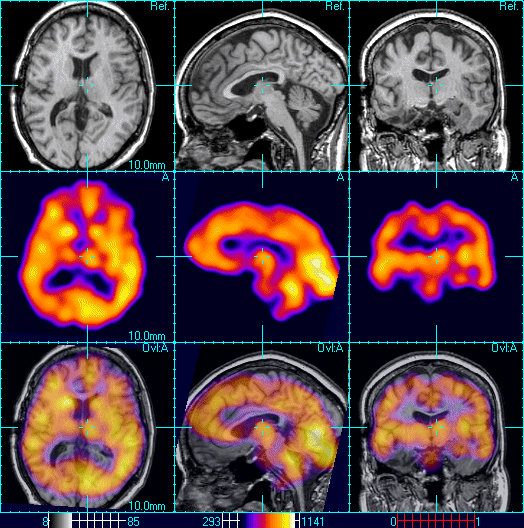

Shows a healthy 3D surface rendering of SPECT information , looking at

Methodology used to fuse MR and SPECT medical images [Color figure can Spect Full Form In Medical A spect scan of the heart is a noninvasive nuclear imaging test. A single photon emission computed tomography (spect) scan is an imaging test that shows how blood flows to tissues and organs. It uses radioactive tracers that are injected into the blood to produce. Spect Full Form In Medical.